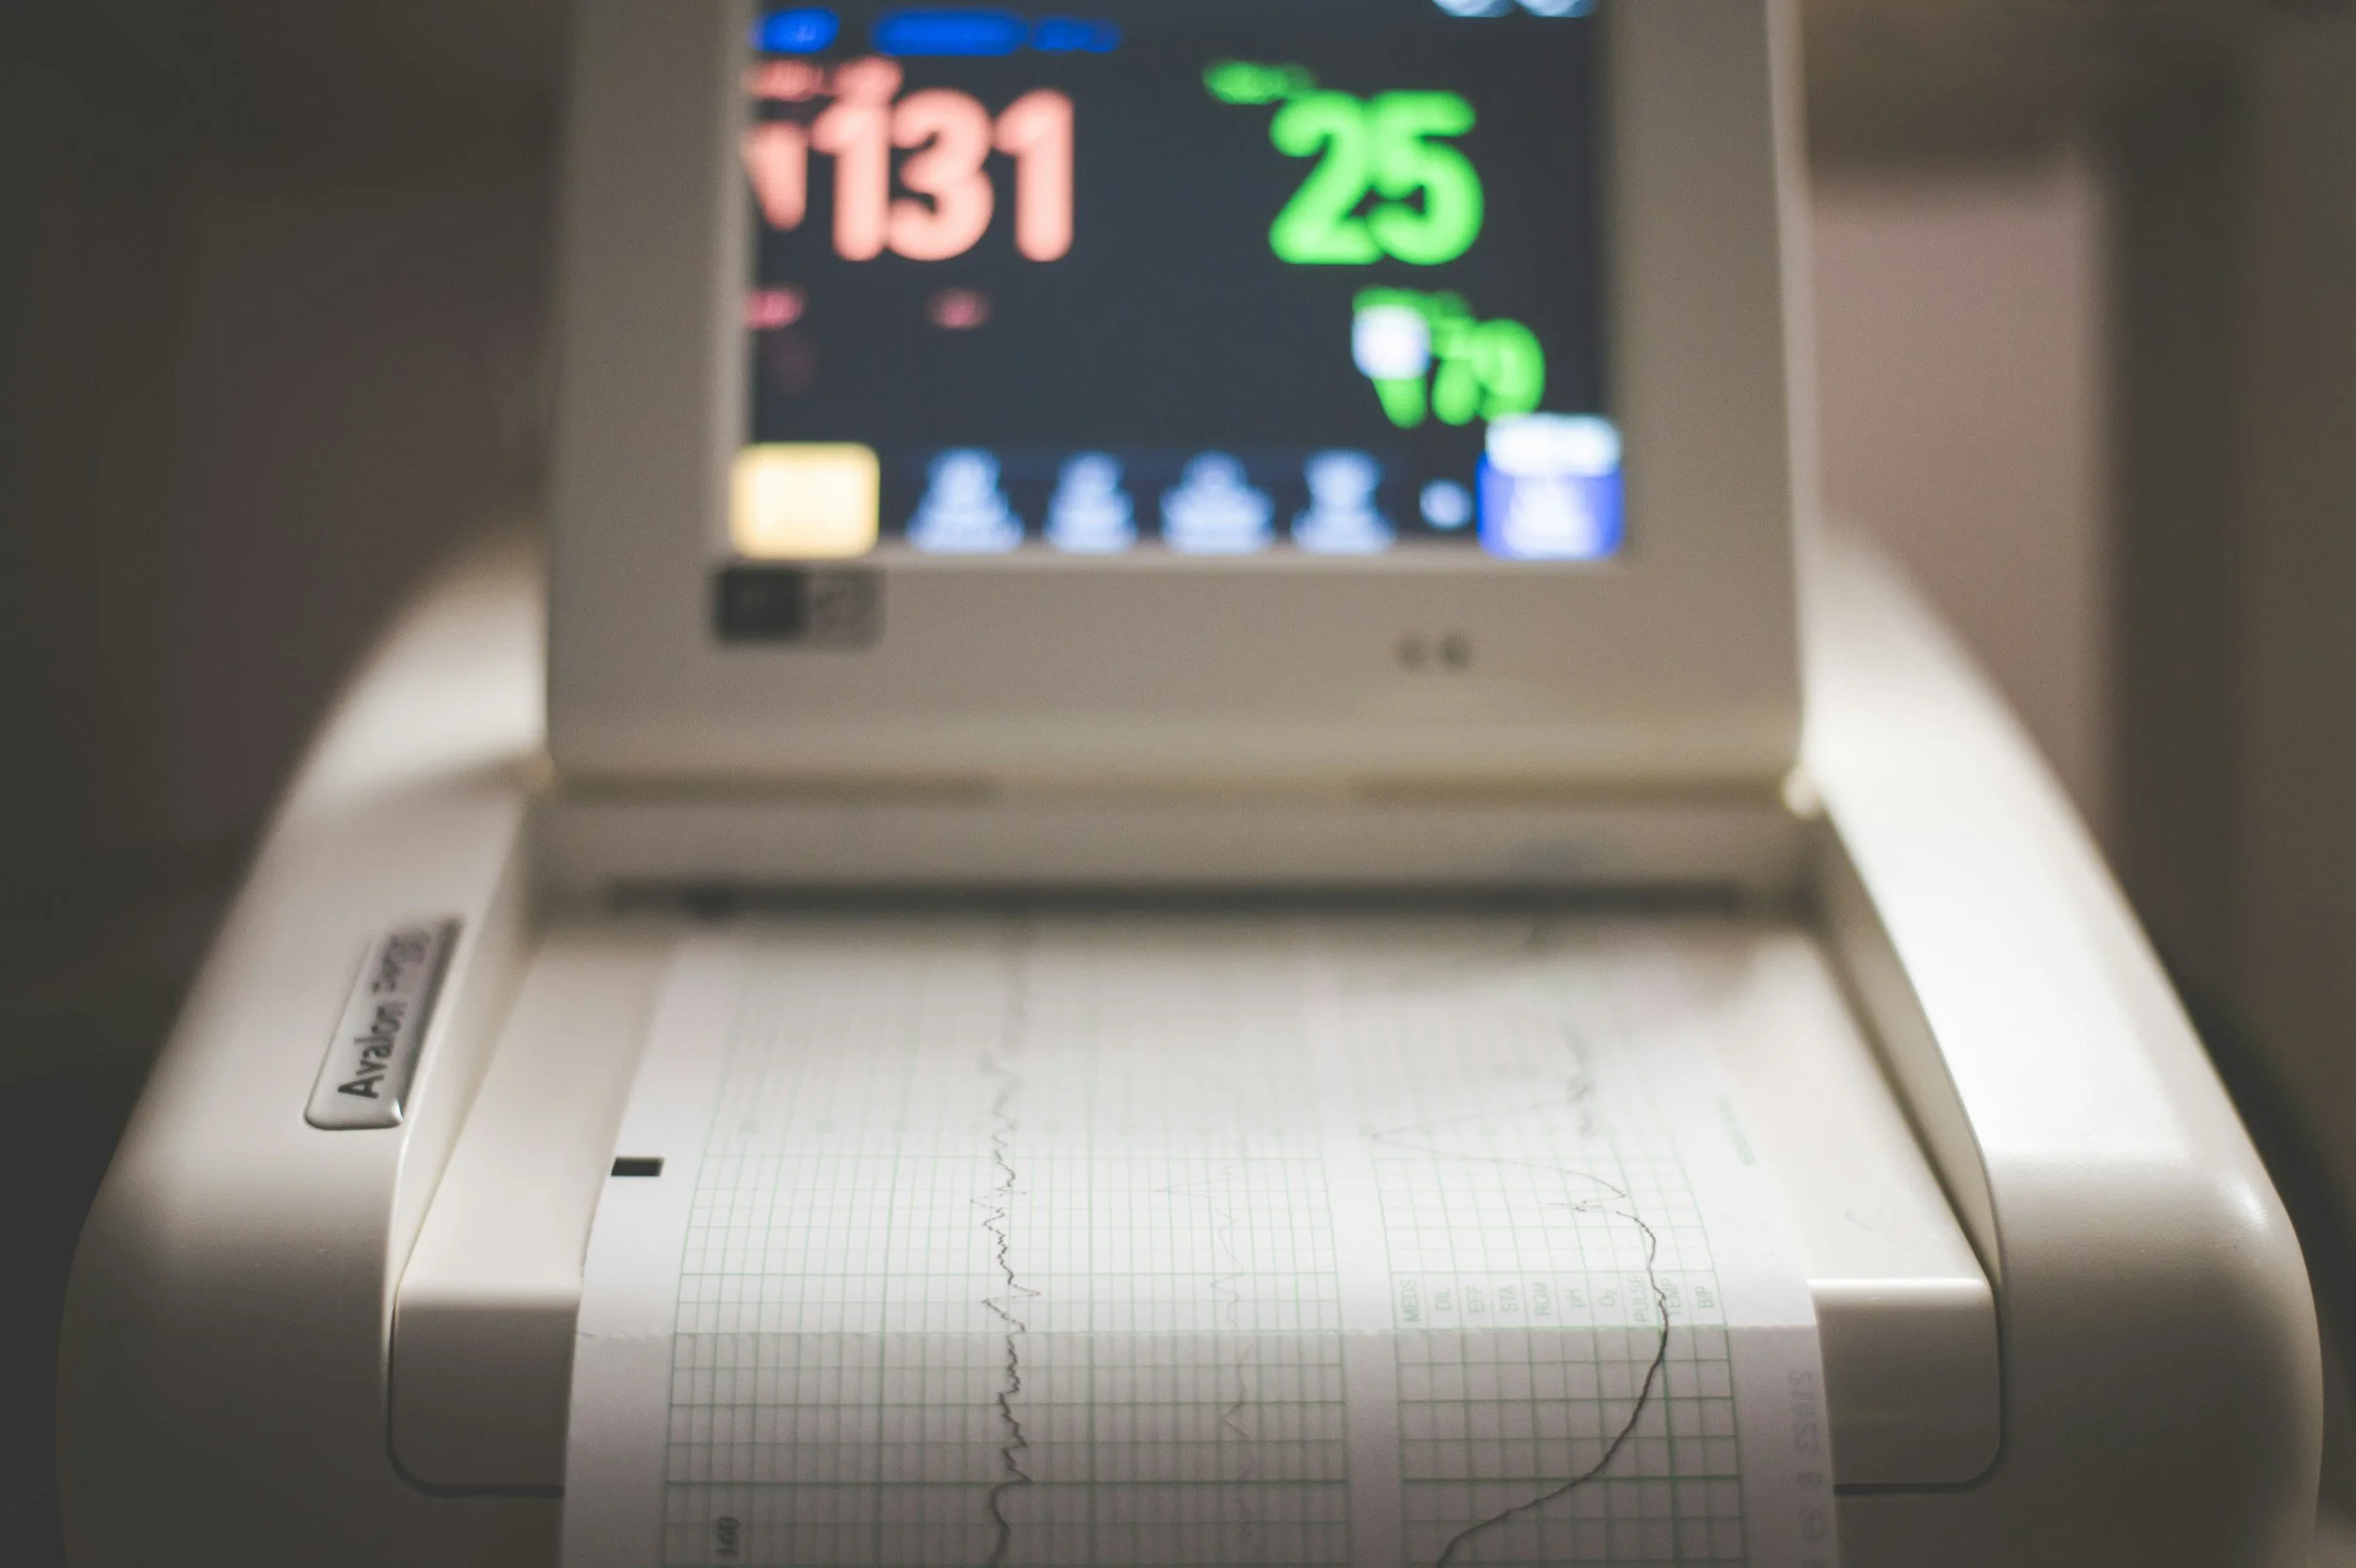

With board certification in fetal monitoring interpretation, you can count on M.E. Legal Nurse Consulting to help you interpret fetal monitoring strips in regard to labor progression and outcomes.

Fetal cord gas interpretation offers objective data on a newborn’s oxygenation and acid-base balance at birth, providing crucial evidence to support or refute claims of fetal distress or compromised care.

Oxygen deprivation during labor, or fetal hypoxia, requires careful assessment of fetal monitoring, clinical interventions, and response times. As an expert witness, I provide objective analysis to both plaintiff and defense teams to evaluate whether the standard of care was met and how care decisions impacted fetal outcomes.

The severity and timing of hypoxic events can influence the extent of brain injury and subsequent motor impairments seen in cerebral palsy. Not all cases of cerebral palsy are directly linked to hypoxia, as there can be other causes such as genetic factors, infections, or brain abnormalities.

In infants, Hypoxic-Ischemic Encephalopathy (HIE) may result from various complications during pregnancy, labor, or delivery—such as placental insufficiency, umbilical cord abnormalities, or birth events that restrict oxygen delivery to the brain. Objective evaluation of these factors is essential for both plaintiff and defense teams to determine whether the standard of care was met and how the timing and management of care influenced potential outcomes.